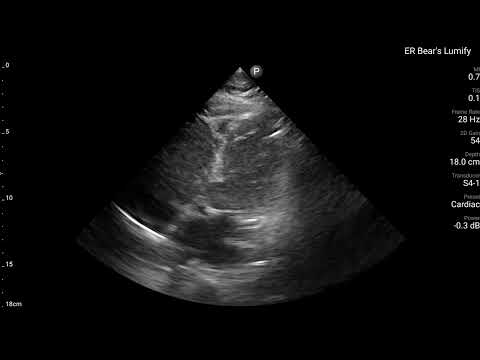

當下有幫病患做echo,讓我們來看看echo有哪些findings?

藉由echo,我們可以看到,LAD支配的Ant.wall幾乎不太動。(請搭配Fig.4安心服用)

ECG在LAD支配位置的Precordial leads出現Subtle STE/PRWP/HATW/此外10分鐘後的dynamic STTC,另外加上echo看到ant.wall有RWMA。這些證據不管怎麼樣都實實在在說明,LAD出現問題了。